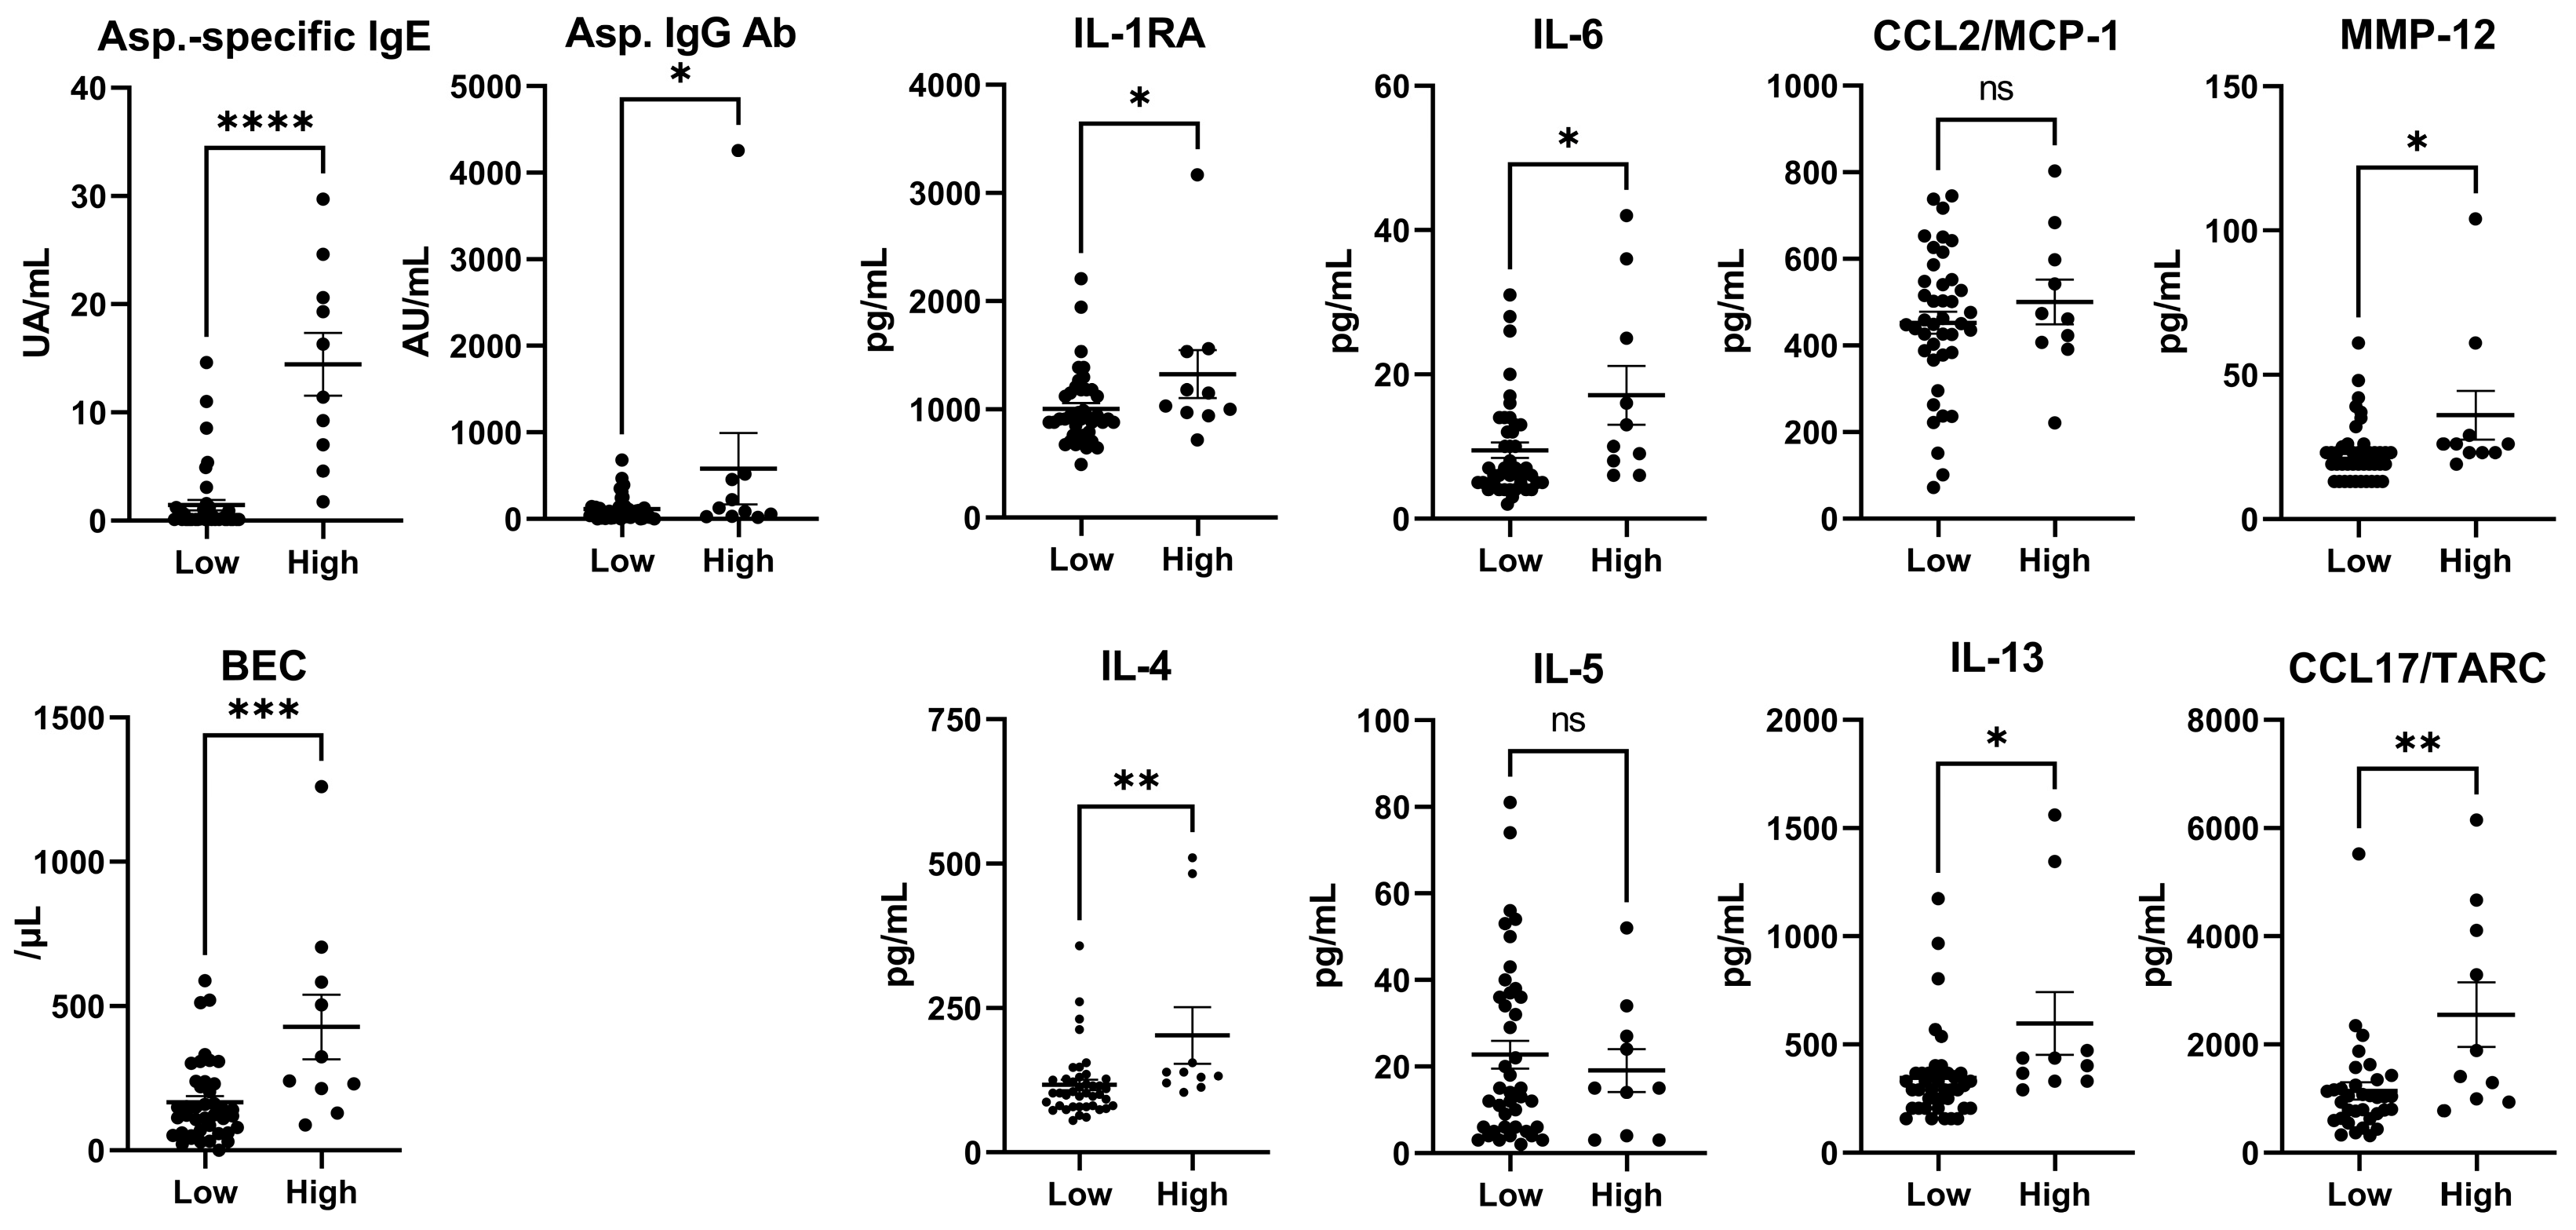

3.4. Cytokines (Total IgE Levels < or ≥500 IU/mL in Patients with CPA)

| Asp.-specific IgE (UA/mL) | 1.4 ± 3.1 | 14.5 ± 9.1 | <0.0001 | **** |

| BEC (/μL) | 166.9 ± 139.0 | 427.6 ± 355.0 | 0.0005 | *** |

| Asp. IgG Ab. (AU/mL) | 113.9 ± 145.9 | 580.1 ± 1304.0 | 0.026 | * |

| IL-1RA | 1004.0 ± 340.3 | 1326.0 ± 697.4 | 0.038 | * |

| IL-4 | 116.9 ± 57.9 | 202.5 ± 155.7 | 0.0062 | ** |

| IL-5 | 22.8 ± 20.7 | 19.1 ± 15.6 | 0.6 | |

| IL-6 | 9.5 ± 6.9 | 17.1 ± 12.9 | 0.013 | * |

| IL-13 | 345.8 ± 207.9 | 597.5 ± 457.2 | 0.011 | * |

| CCL17/TARC | 1131.0 ± 859.4 | 2553.0 ± 1883.0 | 0.0021 | ** |

| MMP-12 | 22.9 ± 10.4 | 36.0 ± 26.7 | 0.012 | * |